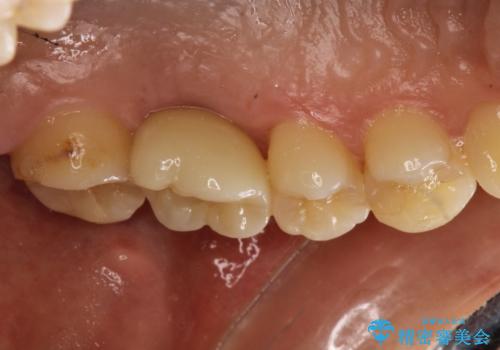

奥歯が割れてしまった! → インプラントによるかみ合わせの回復

→2時手術の後、インプラントレベルの型どりにて上部構造まで完成させる

かぶせものの種類:Bellezza